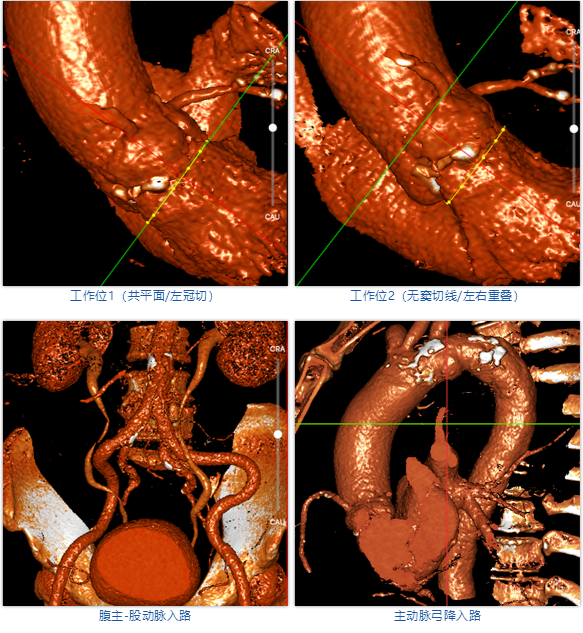

武汉协和董念国团队对该病例进行了缜密探讨,该病例为老年男性,主动脉瓣中重度狭窄,术前左室舒张功能减低。患者病例CT和心超数据显示瓣环瓣周长:90.2mm,瓣下4mm流出道周长:97.5mm,窦部空间相对小,单纯无冠瓣瓣叶钙化,三叶瓣。左冠风险较高,缜密分析瓣叶遮盖率>50%,术中可能存在阻挡风险,需要术中球囊扩张时仔细辨认,并准备冠脉保护策略。综合评估考虑右股动脉更适宜为主入路。经过团队严谨的评估及充分的讨论,决定先行25mm球囊预扩并进一步确认冠脉风险,并准备TAV29和TAV32规格的ProStyle预装式可回收TAVR系统。

术者采用患者右侧主入路,顺利完成导丝和猪尾跨瓣等准备工作。进Landerquist超硬导丝,采用25mm球囊进行预扩,仔细评估冠脉风险后,决定对冠脉采取保护措施。根据球囊扩张情况,术中决定使用金仕生物的ProStyle预装干瓣TAV32。打开包装后,很迅速的完成了瓣膜和系统植入前的准备。输送过程系统和瓣膜轻松过弓并顺利跨瓣;开始初步释放,然后快速起搏下释放,发现位置略高后进行回收,重新定位后最终成功完成释放。反复造影发现冠脉存在阻塞风险,武汉协和团队按照风险预案在左冠植入4.0*18mm支架进行保护。术后显示左右冠脉血液灌注通畅,术后超声测量峰值流速1.45m/s,峰值压差8mmHg,几乎无瓣周漏。入路闭合顺利,无心脏及血管并发症,手术成功。

该团队尚小珂教授同时表示:金仕生物ProStyle新一代预装干瓣全可回收TAVR系统首例采用大瓣膜植入成功,证明该TAVR系统具有良好的过弓性能和可操作性,其安全性和有效性在接下来的确证性研究中将进行大样本量的验证。武汉协和医院结构性心脏病TAVR团队近期已成功开展多项前沿的创新器械与技术,为结构性心脏病患者提供丰富多样的治疗选择。